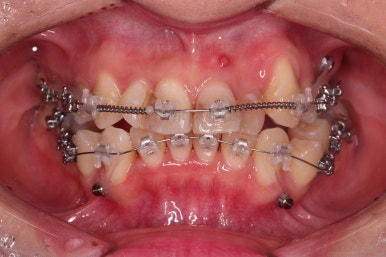

사용한 장치 : 자가결찰 세라믹(엠파워 클리어, Empower clear) + 미니스크류

충치치료르 한다고 몇 달을 기다리다 보면 교정 후에 해야 하는 충치는 더 늦어지기 때문에 우선 교정장치부터 부착하고 충치치료는 병행해 가면서 하기로 했습니다.

덧니를 개선하기 위해서 추가적으로 작은 어금니를 발치했고요.

윗니 앞니는 급한대로 신경치료 부터 진행했고, 최종 심미보철은 교정 후 미루었습니다.

공간을 줄여나가고 순차적으로 충치치료도 마무리 해갑니다.